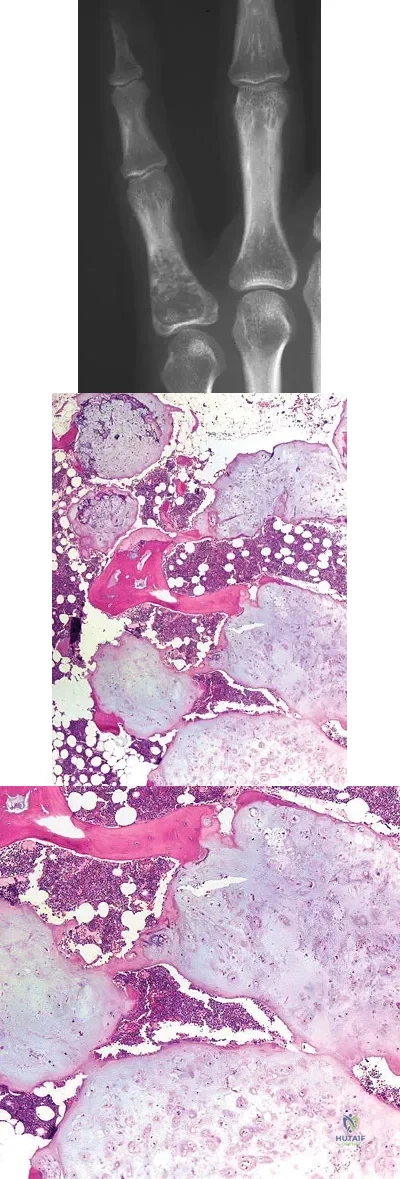

Question 75

A 28-year-old woman has had pain in her hand and mild swelling of the little finger for the past 2 months. A radiograph is shown in Figure 41a, and the biopsy specimen is shown in Figures 41b and 41c. What is the most likely diagnosis?

Explanation